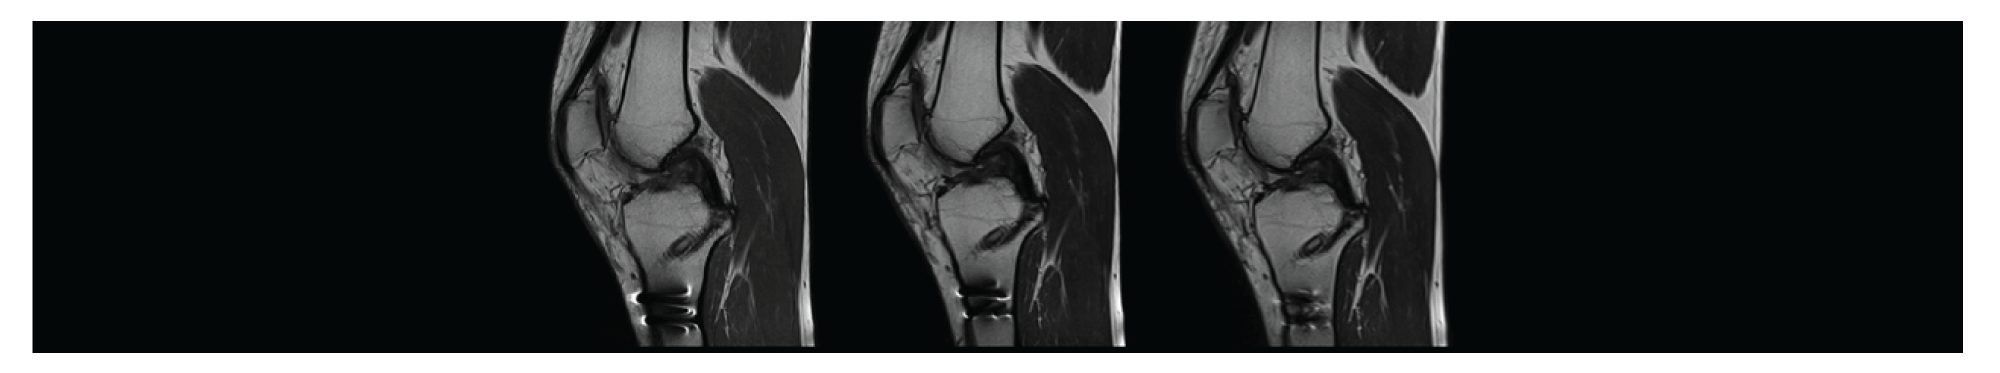

ระบบกระดูกและข้อ

MRI กระดูก ข้อ คือ ให้ภาพที่คมชัดและละเอียด แยกความแตกต่างของเนื้อเยื่ออ่อนได้ดี ทำให้สามารถวินิจฉัยโรคได้แม่นยำยิ่งขึ้น โดยเฉพาะ เส้นเอ็น, กระดูกอ่อน หรือหมอนรองกระดูก นอกจากนี้ยังปลอดภัย เพราะไม่ใช้รังสี เหมาะกับการตรวจ

การบาดเจ็บของข้อ: เช่น การฉีกขาดของเส้นเอ็น, กระดูกอ่อน หรือหมอนรองกระดูก

ความผิดปกติของกระดูกสันหลัง: เช่น กระดูกสันหลังหัก, หมอนรองกระดูกทับเส้นประสาท, เนื้องอก หรือการติดเชื้อ

เนื้องอกของกระดูก

การติดเชื้อในกระดูก

MRI รุ่น MAGNETOM Altea มี "WARP" คือ เทคนิคที่ใช้ลดสิ่งแปลกปลอม (Artifacts) ที่เกิดจากโลหะ ซึ่งทำให้เกิดภาพบิดเบี้ยว เทคนิคนี้ช่วยปรับปรุงคุณภาพของภาพเมื่อทำการสแกนผู้ป่วยที่มีอุปกรณ์ทางการแพทย์ที่เป็นโลหะ